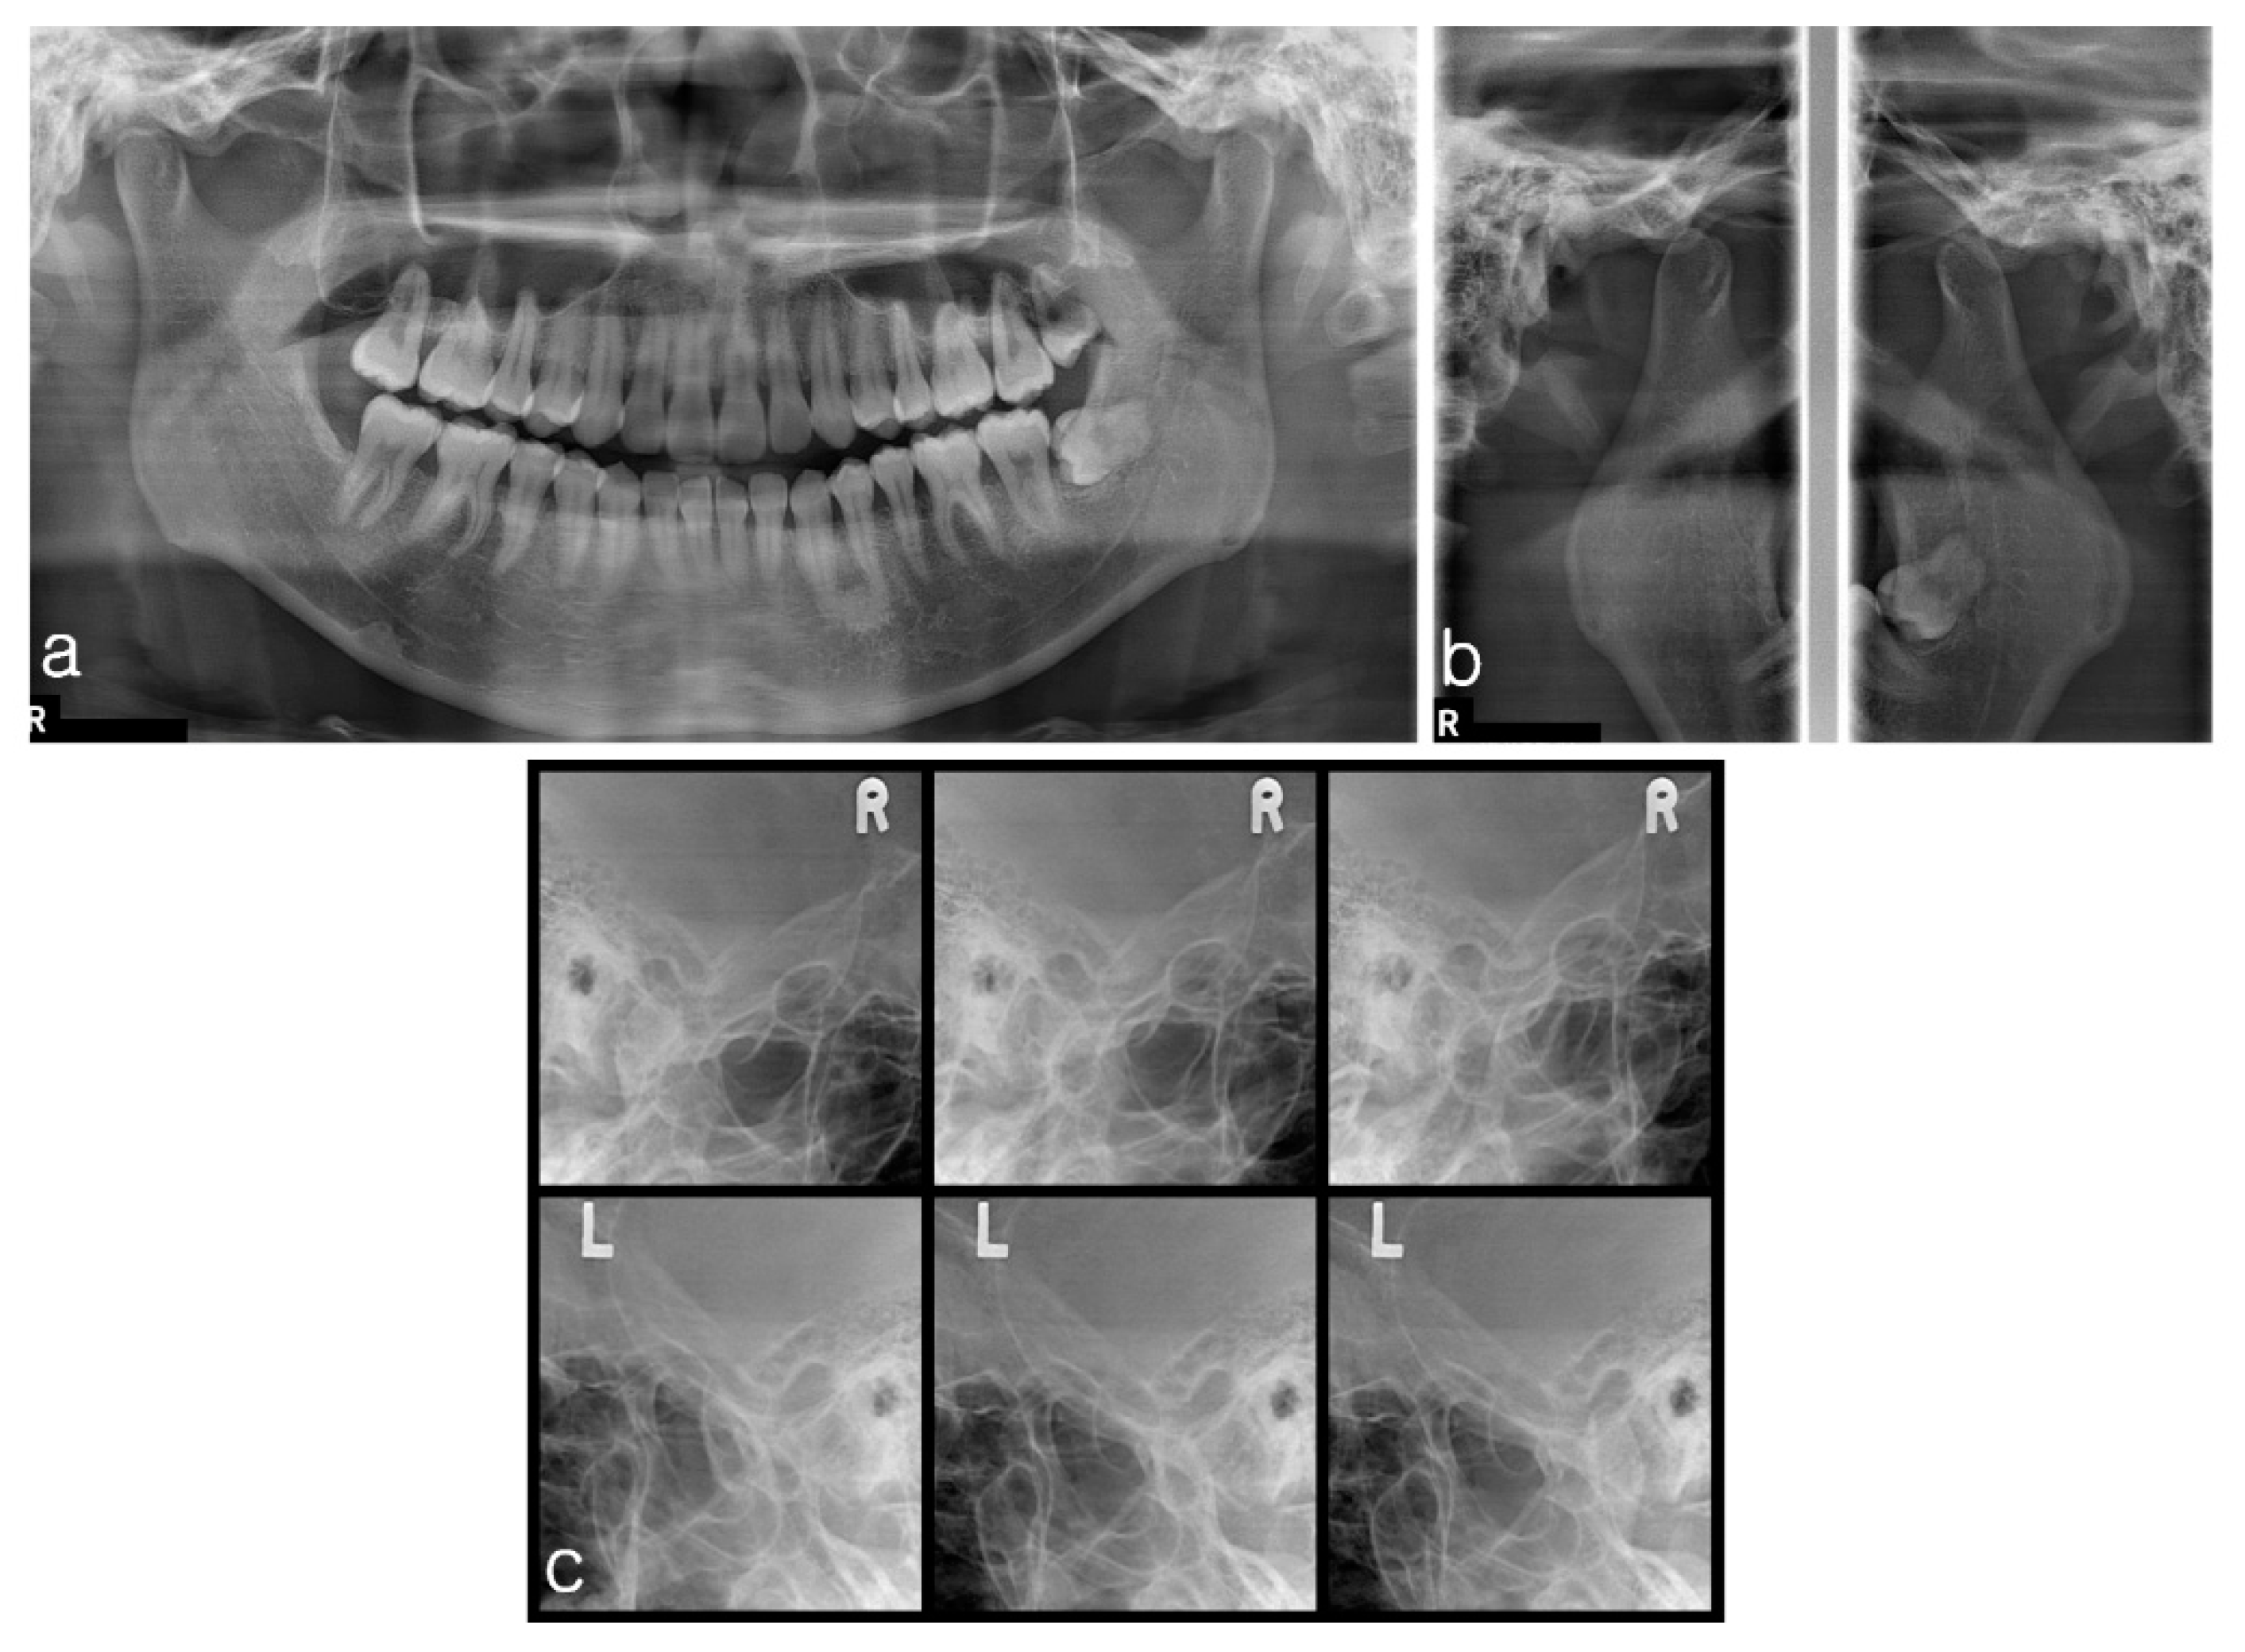

2.1.2. Imaging

2.2.2. Imaging